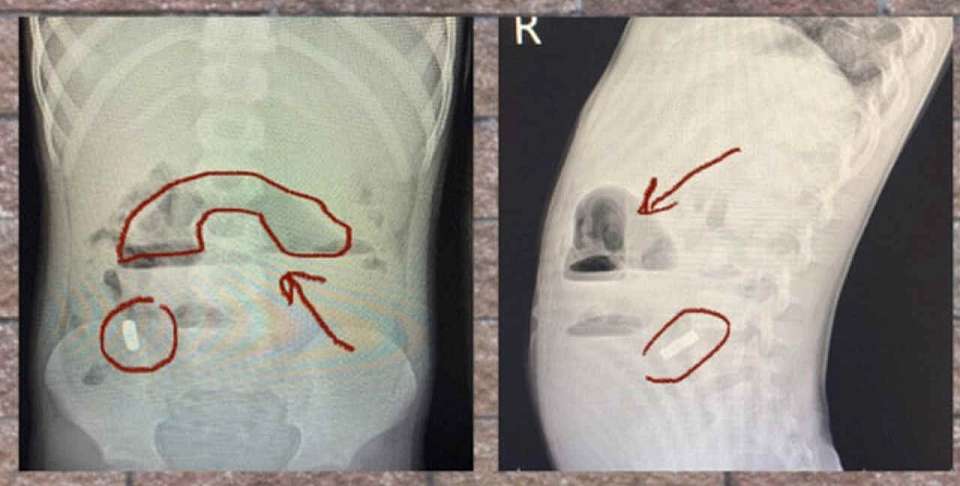

Как сообщили в медучреждении, ребёнок жаловался на боль в животе. В больницу его привезли родители. Мальчика после осмотра госпитализировали. Рентген и УЗИ показали, что в кишечнике находятся магниты, которые, притянувшись друг к другу, вызвали непроходимость.

Срочную операцию провели врачи ВОДКБ №2. Они вытащили из брюшной полости мальчика инородные тела.